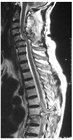

1. 高エネルギー外傷による脊椎損傷が疑われる場合には、呼吸状態、循環動態などの全身状態評価と必要な救急救命処置を優先し、その後に神経学的評価・画像評価を行うことが推奨される。

1. 頭蓋頚椎、頚胸椎、胸腰椎の各移行部での脊椎損傷は他の臓器との重なりが多く、単純X線では見落とされることがあり、CTによる評価が推奨される。

1. 高齢化に伴い強直性脊柱や骨粗鬆症を基盤とした脊椎損傷の比率が上昇しており、その病態、損傷形態に応じた治療法、手術法が求められる[1]